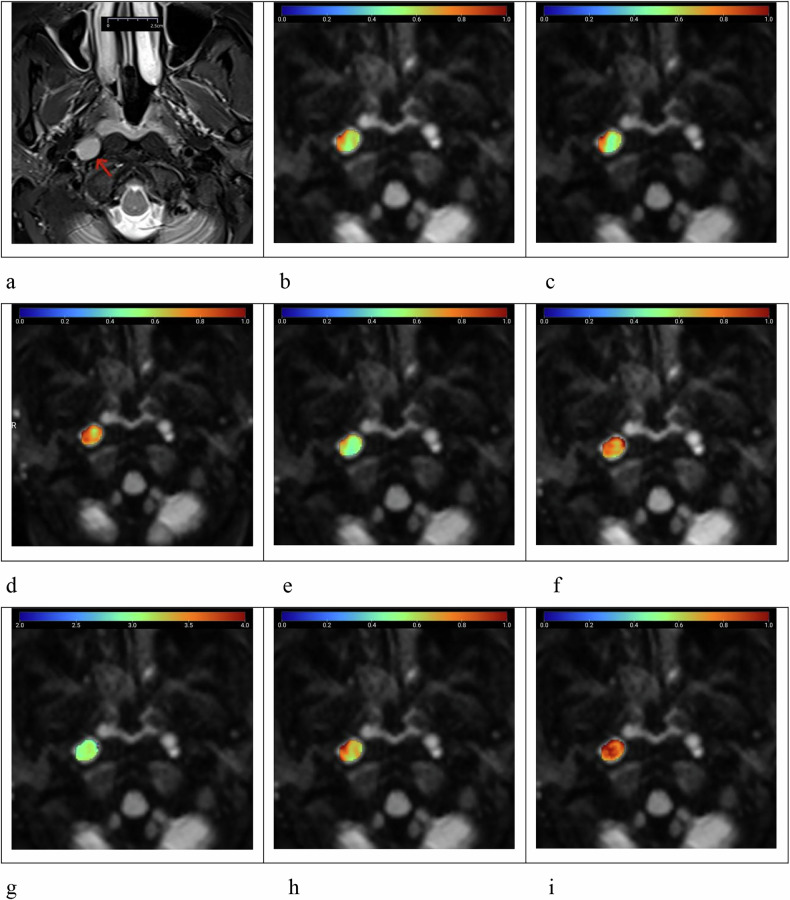

Methods: Fifty-nine patients with 68 RLNs (23 benign and 45 metastatic) were enrolled. All patients underwent DWI with 12 b-values. Diffusion data were reconstructed using conventional DWI, SEM, FROC, and CTRW models, yielding nine parameters: apparent diffusion coefficient (ADC), distributed diffusion coefficient (DDC)SEM, αSEM, DFROC, βFROC, μFROC, DCTRW, αCTRW, and βCTRW. Diffusion parameters and morphological features were compared using Mann-Whitney U, independent sample t, or χ2 tests. Logistic regression analysis was performed to identify the best diffusion indicator for classification and to develop a multiparameter model combining morphological features. Area under the receiver operating curve (AUC) and DeLong tests were used.

Results: Significant differences in diffusion parameters were found between benign and metastatic RLNs, except for αCTRW (p ≤ 0.022). Benign RLNs exhibited higher ADC, DDCSEM, DFROC, and DCTRW, while metastatic RLNs had higher αSEM, βFROC, μFROC, and βCTRW. Multivariate logistic regression analysis identified βCTRW as the optimal single diffusion indicator (AUC = 0.913). The combined model of βCTRW with morphological features further improved diagnostic performance and yielded an AUC of 0.948.